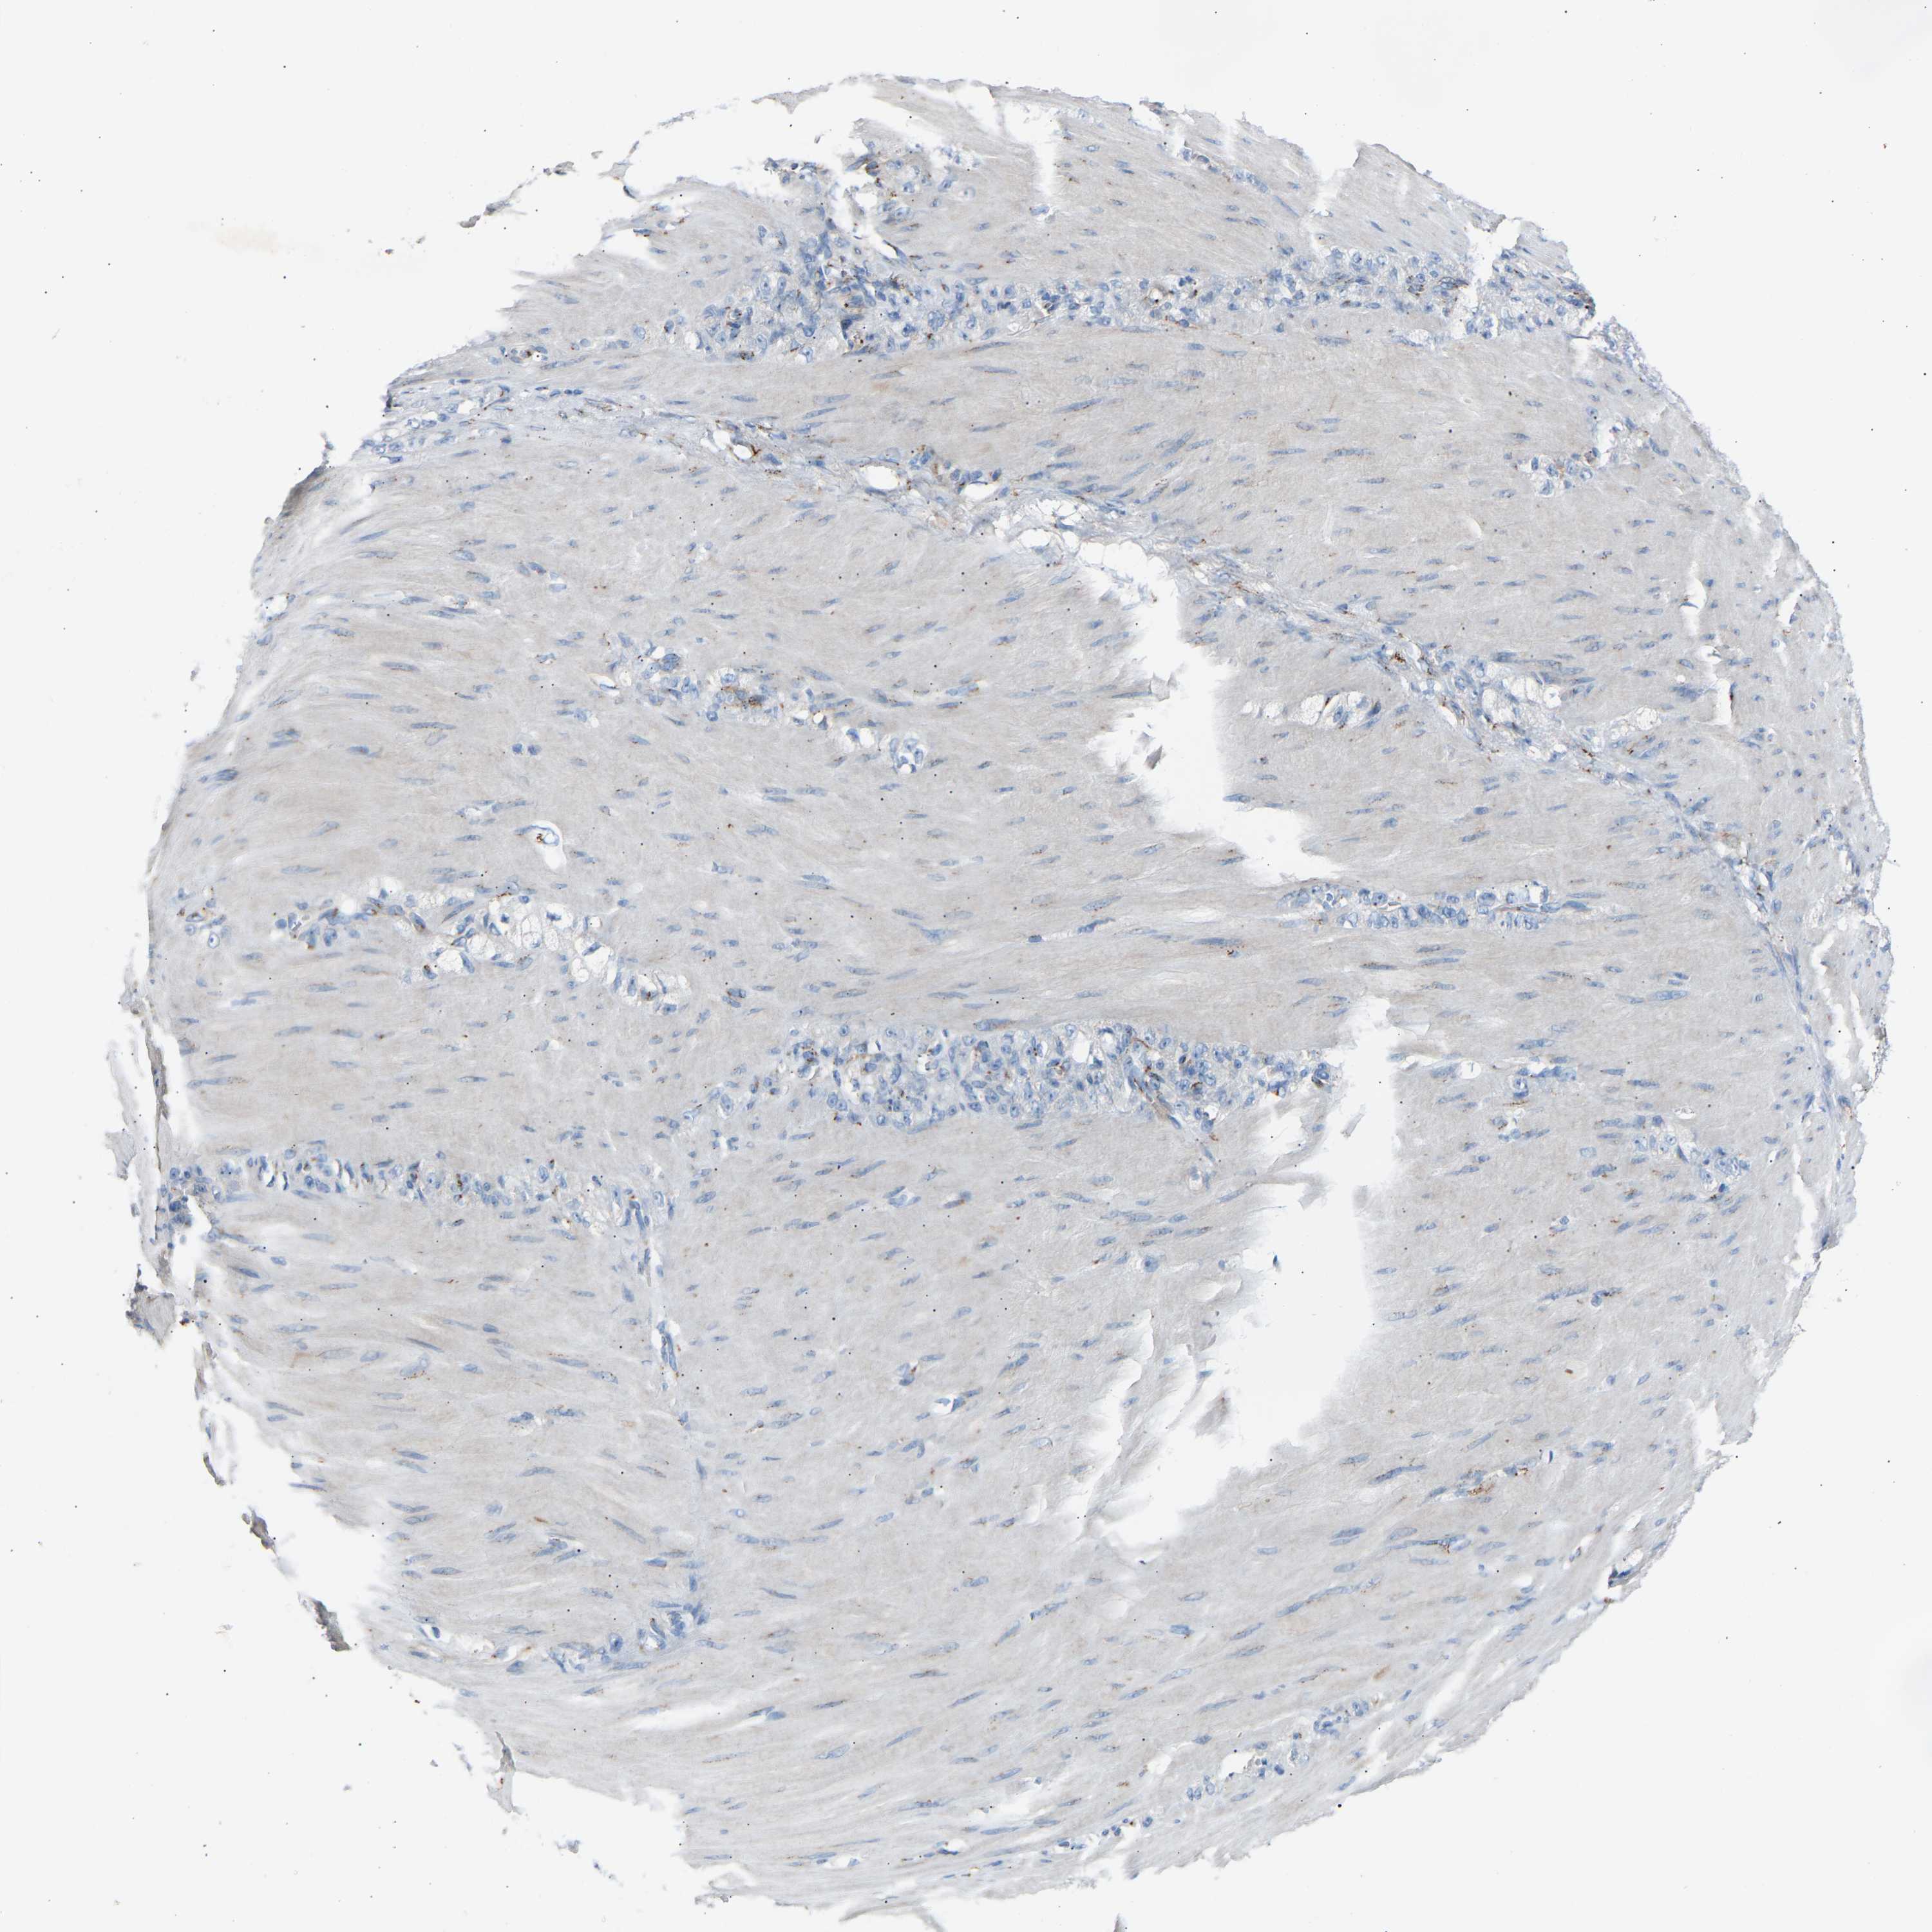

STOMACH CANCER - Protein expressioni

A mouse-over function shows sample information and annotation data. Click on an image to view it in a full screen mode. Samples can be filtered based on level of antibody staining by selecting one or several of the following categories: high, medium, low and not detected. The assay and annotation is described here.

Antibody stainingi

Antibody staining in the annotated cell types in the current human tissue is reported as not detected, low, medium, or high, based on conventional immunohistochemistry profiling in selected tissues. This score is based on the combination of the staining intensity and fraction of stained cells.

Each image is clickable and will lead to virtual microscopy that enables deeper exploration of all samples and also displays staining intensity scores, fraction scores and subcellular localization as well as patient and tissue information for each sample.

Antibody HPA020060

Staining

High

Medium

Low

Not detected

Intensity

Strong

Moderate

Weak

Negative

Quantity

>75%

75%-25%

<25%

None

Location

Nuclear

Cytoplasmic/membranous

Cytoplasmic/membranous,nuclear

Adenocarcinoma, NOS